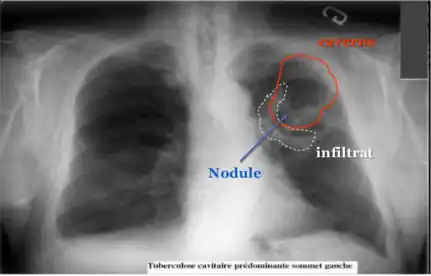

Diagnostic radiologique

La modalité de diagnostic radiologique se révèle très utile et indiquée comme étant un examen de première intention en cas de tuberculose pulmonaire et ostéoarticulaire[77]. Cela est justifié par les images radiologiques plus ou moins spécifiques à la tuberculose. La littérature rapporte que la spécificité varie de 27 à 81 % selon l’étude. Les imageries idéales et révélatrices de la tuberculose répondent à certains attributs dont le premier est lié au siège. En raison de l’affinité que les BK ont envers les régions aérées, la lésion radiologique est souvent observée dans les parties hautes des poumons. Néanmoins, l’image radiographique peut contenir différentes formes :

- infiltrat : traduisant des lésions débutantes de l’infection via une opacité peu dense, hétérogène et étendue ;

- nodule : granulome de taille variable, isolé ou groupé ;

- tuberculome : nodule isolé pseudotumoral ;

- caverne : excavation par perte de substance au sein d’un infiltrat, aux parois épaisses.

Les cavernes sont une complication fréquente de la tuberculose pulmonaire[54]. On appelle caverne une cavité creusée au sein du parenchyme pulmonaire[55]. Les bacilles tuberculeux se développent initialement dans le poumon sous forme de nodules, appelés granulomes, qui sont peu à peu entourés de lymphocytes et de macrophages destinés à contenir l'infection[54]. Un granulome peut évoluer soit vers la disparition sans cicatrice, soit vers la caverne, sans que les mécanismes sous-jacents soient compris en totalité[55]. Les vestiges de macrophages détruits occupent le centre du granulome et forment la majeure partie de la nécrose caséeuse[55]. Chez certains patients, cette nécrose caséeuse se liquéfie et devient un milieu de culture adapté aux bacilles, qui prolifèrent. Des enzymes protéolytiques érodent alors la capsule fibreuse située en périphérie du granulome, et son centre liquide peut alors se vider peu à peu[55]. Lorsqu'une caverne tuberculeuse arrive en communication avec l'arbre bronchique, la dissémination des bacilles dans l'air expiré augmente la contagiosité[54],[56]. Par ailleurs, la quantité importante de bacilles contenus dans les cavernes favorise le développement de résistances aux anti-tuberculeux[56].